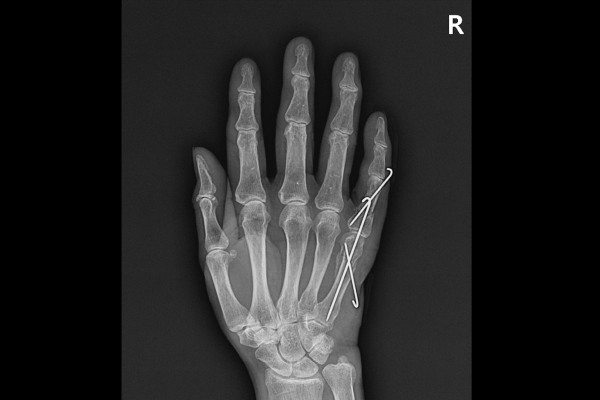

환자분께 현재 손가락 상태와 수술적 치료의 필요성 수술의 방향성을 설명드렸고, 수술적 치료인 우측 손 중수골 및 새끼손가락 골절 도수정복술 및 핀고정술(Closed reduction c pinning for Fx. 5th MC neck + 5th prox. phal hand Rt.)을 시행하였습니다.(환자분의 경우 손가락 모양이 꺾여서 들려있었고, 계속해서 소를 키워야하기 때문에 빠른 회복이 필요하여 수술적 치료가 불가피하였습니다.)

실시간 X-RAY인 C-ARM을 이용하여 확인하면서 수술을 진행하였고, 골절선을 맞춘 후 핀으로 고정해줍니다.

수술 후 X-RAY를 보면 골절되었던 새끼손가락 중수골, 근위지골이 잘 고정되어있는 것을 확인할 수 있습니다.

새끼손가락 골절 수술 후 재활기간을 알아보면 약 4주간은 깁스 착용 후 손을 구부리지 않는 것이 좋으며, 4주가 지나면 손가락을 구부렸다 폈다하는 운동을 시작합니다. 핀은 6주가 지난 시점에 뽑게됩니다. 환자분께서는 핀도 뽑으셨고 잘 회복되셔서, 이상 없이 일상으로 복귀하였습니다.